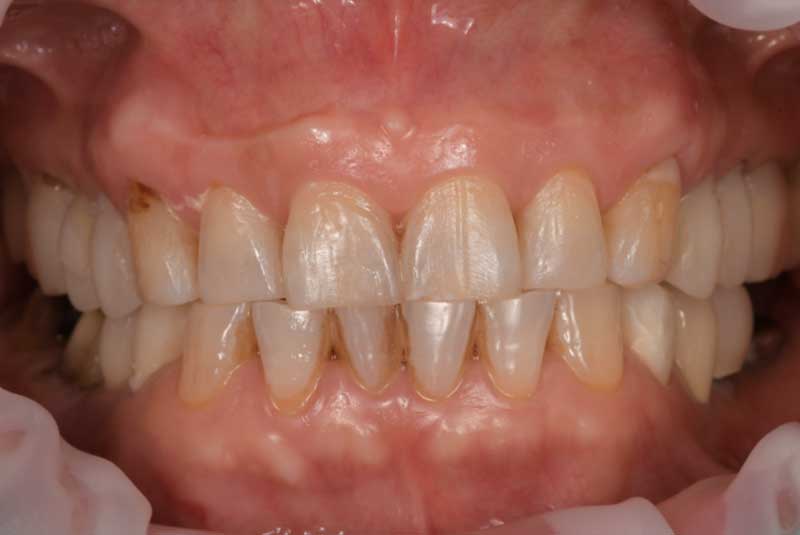

The patient had her implants placed 20 years ago. Four implants, particularly in the maxilla, were not positioned ideally for me to utilize and restore, while the four implants in the mandible were outdated and no longer functional. The patient's primary concern is to restore both function and aesthetics.

All on 6: Facial cut back (PFZ) Zirconia Full arch prosthesis for Maxilla and Mandible Before & After

All on 6 for both arches Implants (#3,4,6,11,13,14,18,21,22,27,28,31)